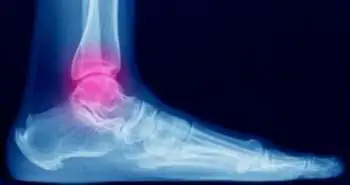

Combining the osteotomy techniques found beneficial in reconstructing malunited medial impacted ankle fractures

Supramalleolar osteotomy, in combination with an intra-articular osteotomy, shows promising results in reconstructing malunited medial impacted ankle fractures.

The malunited medial impacted ankle fractures with varus ankle deformity can be effectively treated using supramalleolar osteotomy when combined with an intra-articular osteotomy, an analysis of a retrospective study published in the Journal, Foot & Ankle International.

The patients who were reported to have medial impacted ankle fracture from January 2011 and December 2014 were selected. These patients were classified into four classes; type A fractures, type B fractures with the AO classification, 44A2 and 44B3 and went through the operation. The pain, clinical and radiographic outcomes were assessed using visual analog scale (VAS), the Olerud and Molander Scale, and the modified Takakura classification stage, respectively.

After the treatment, the tibial ankle surface (TAS) angle and talar tilt angle (TTA), the radiographic variables showed a significant difference from the baseline. However, no difference was noticed within the mean tibial lateral surface (TLS). The average Olerud and Molander Scale score and VAS also showed an improvement from the baseline. On the other hand, the modified Takakura classification stage reflected no difference from the baseline.

All the above-evaluated results indicated the considerable importance of supramalleolar osteotomy combined with an intra-articular osteotomy.